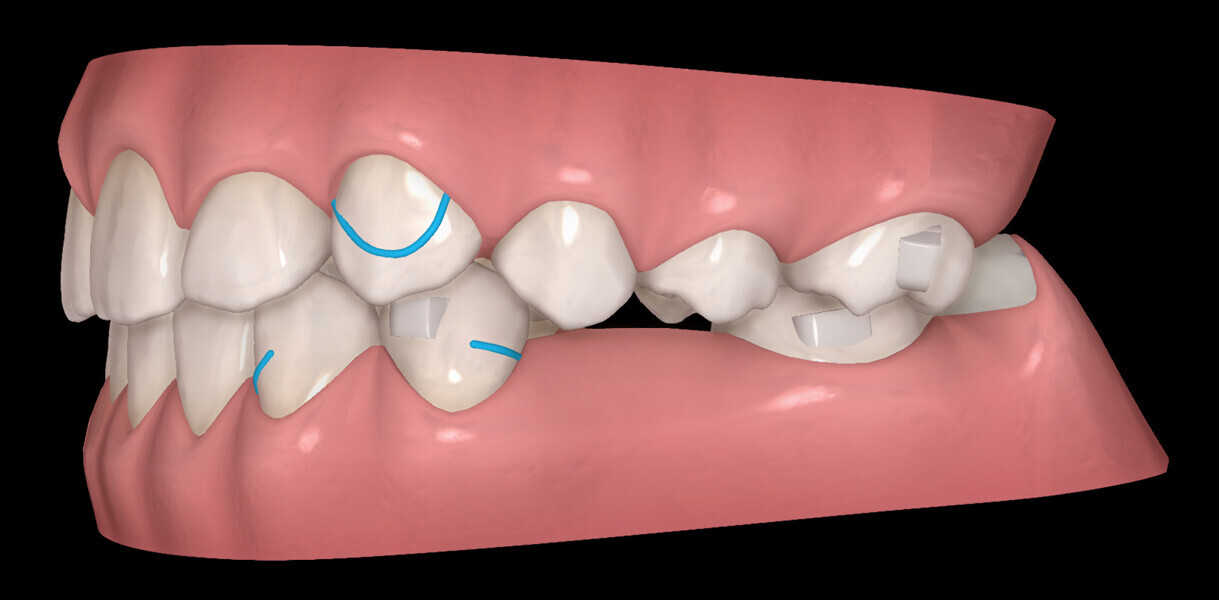

The digital treatment plan (ClinCheck) provided 18 aligners in each arch. The treatment objectives were focused on aligning and levelling the mandibular arch without excessively proclining the mandibular incisors, in order to control the Class III skeletal malocclusion by means of interproximal reduction and slicing of tooth #85. In the maxillary arch, the treatment plan focused on space creation for tooth #13 by distal rotation of the maxillary right molar and mesialisation of the maxillary right lateral incisor simultaneously to centre the midlines. Class II elastics were planned to control distal movement on the right side, and triangular elastics on the high canine were planned on the left side with button cutouts for the aligners. Lateral and posterior maxillary torque were planned to be close to 0° to achieve wider arch design and ideal intercuspation. No digital over-engineering was planned in the set-up, and lingual attachments according to personal preference were placed in the maxillary arch for aesthetic and biomechanical reasons (Figs. 15–19). Eruption compensation for tooth #13 was employed. Because of the age of the patient, the aligners were changed every seven days over the treatment period of less than five months.

At the end of the first stage of aligner treatment (Figs. 20–24), the auxiliary phase began with the bonding of two MTAs on the maxillary right premolars. A 0.016-in Australian archwire, shaped into a cantilever configuration, was then inserted into the MTAs, and a cutout was created on the final aligner. To prevent rotation, the archwire was cinched distal to tooth #15 and the cinch covered with composite.